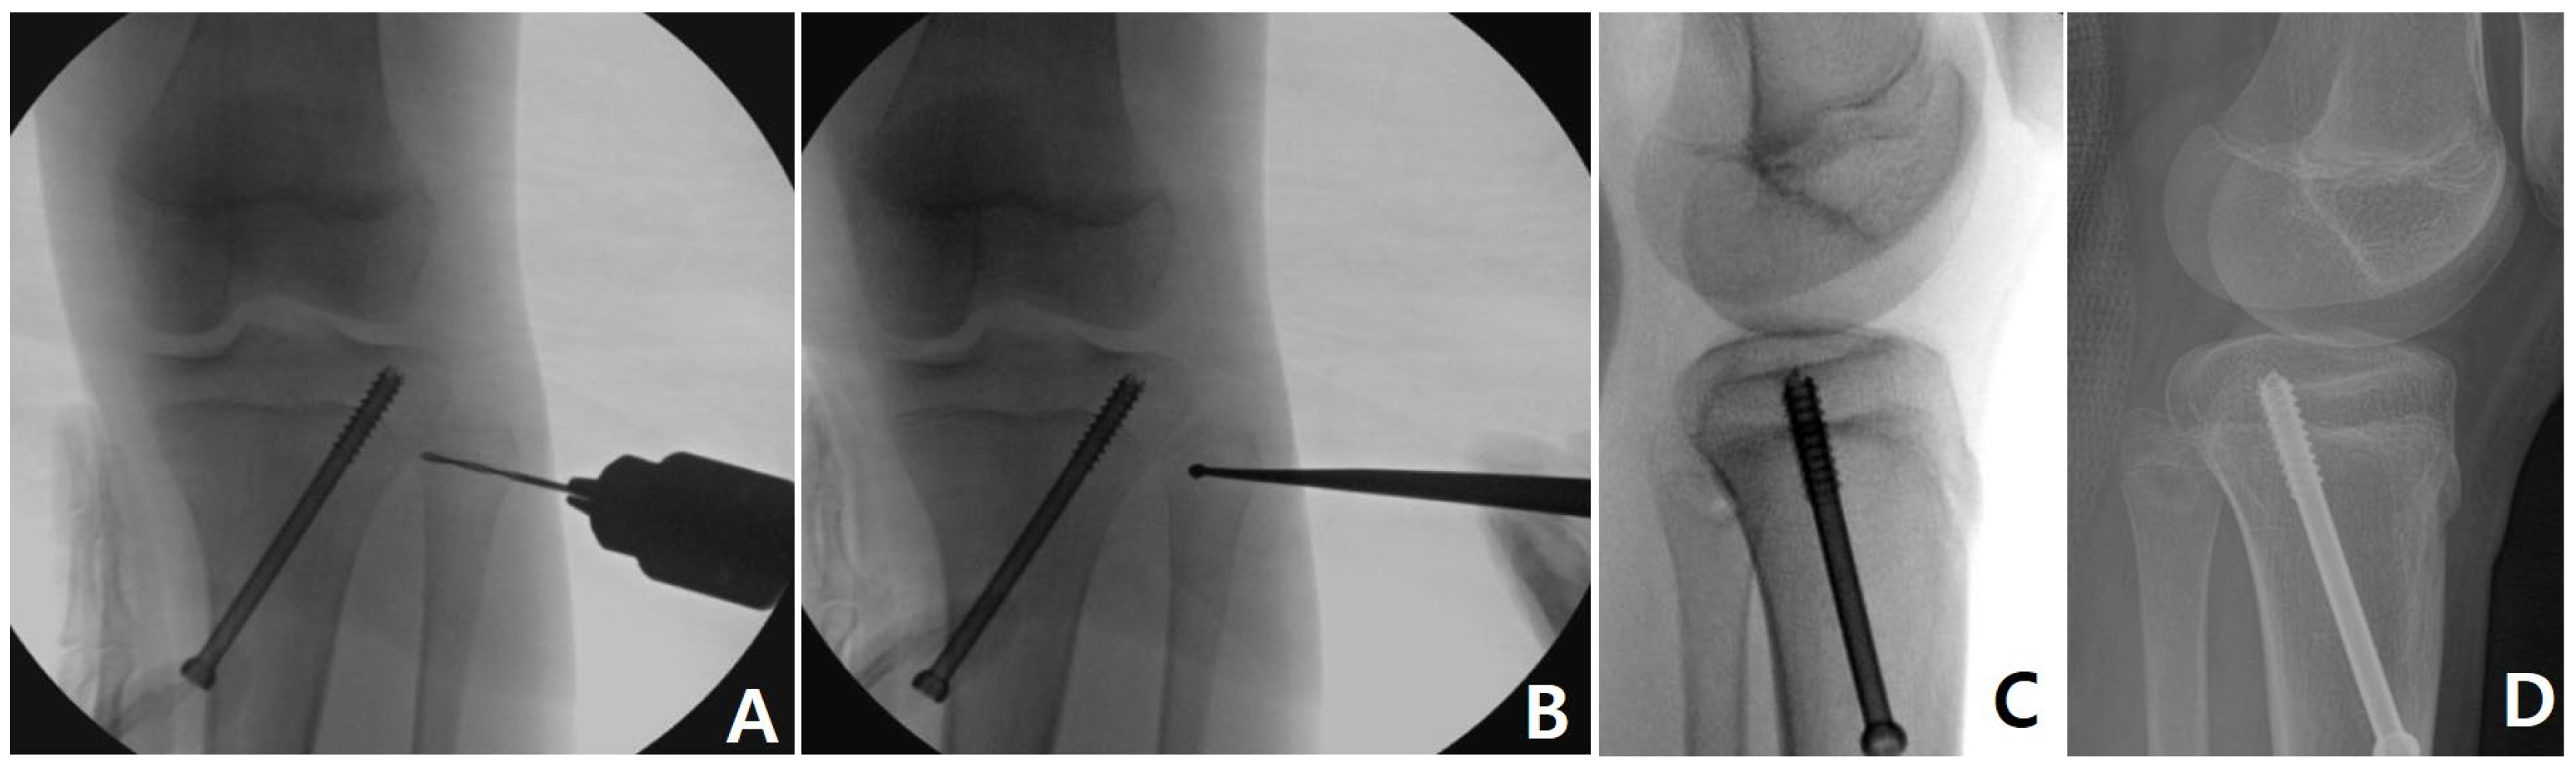

2.2. Surgical Technique